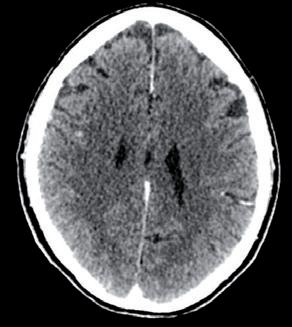

La paziente ha pertanto avviato una seconda linea di trattamento con T-DXd, ottenendo una progressiva riduzione delle lesioni meningee note ai successivi controlli mediante RM, fino ad arrivare a una situazione di stabilità che si mantiene tuttora a 24 mesi dall’avvio del trattamento (figura 1).

Figura 1. Immagini RM prima dell’avvio del trattamento e dopo 6 mesi.